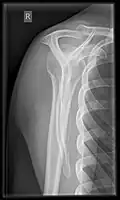

Fracture

Fractures of shoulder bones can include clavicular fractures, scapular fractures, and fractures of the upper humerus.

Imaging of the shoulder includes ultrasound, X-ray and MRI, and is guided by the suspected diagnosis and presenting symptoms.

Conventional x-rays and ultrasonography are the primary tools used to confirm a diagnosis of injuries sustained to the rotator cuff. For extended clinical questions, imaging through Magnetic Resonance with or without intraarticular contrast agent is indicated.

Hodler et al. recommend starting scanning with conventional x-rays taken from at least two planes, since this method gives a wide first impression and even has the chance of exposing any frequent shoulder pathologies, i.e., decompensated rotator cuff tears, tendinitis calcarea, dislocations, fractures, usures, and/or osteophytes. Furthermore, x-rays are required for the planning of an optimal CT or MR image.[25]

X-ray

Projectional radiography views of the shoulder include: